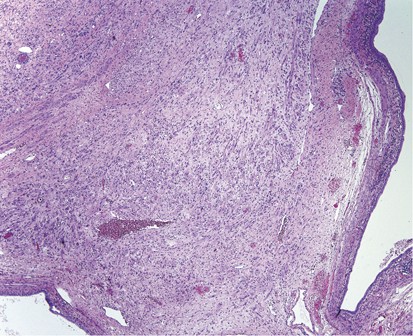

The mass containing the rhabdomyomatous tumors varied from 3.3–17.5 cm with the cut surfaces being solid and cystic, the former varying from tan to yellow to gray and having firm to soft consistencies. On microscopic examination, all of the retroperitoneal lymph-node dissection specimens except for one contained teratomatous elements in addition to the rhabdomyomatous tumors. These included the usual array of interwoven glandular structures, cartilaginous nodules, fibromuscular stroma, and occasional other tissue types. The rhabdomyomatous tumors measured 0.8–5 cm (the two largest estimated from the measured tumor size on the slides and the number of involved slides, see Table 1). They grew as large nodules (Figure 1) to dissecting aggregates (Figure 2) of differentiated rhabdomyocytes, with the former having circumscribed interfaces with the surrounding tissue (Figure 3) and the latter showing peripheral infiltration between teratomatous elements (Figure 4). The cells had either round, regular profiles with centrally placed, spherical nuclei (Figure 5) or elongated, tubular profiles with peripherally placed nuclei (Figure 6). Such myotubes commonly showed nuclear aggregation in a common sarcoplasm (Figure 6) and were identified at least focally in every case. The nuclei showed mild to moderate pleomorphism and had small to moderate-sized nucleoli. Degenerate-type hyperchromasia occurred focally in two cases (Figure 7). Mitotic activity was not seen. In no case was there evident necrosis of the rhabdomyomatous elements. There was no evidence of a primitive, undifferentiated tumor component associated with the rhabdomyocytes.

A large, circumscribed nodule of rhabdomyomatous tumor interfaces with adjacent smooth muscle (right).

This nodule of rhabdomyomatous tumor has a circumscribed interface with adjacent fibrous tissue containing foamy histiocytes (left).